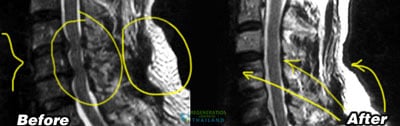

The objectives of our spinal injury treatment center is to help repair damage in a natural and safe manner. Our treatments take place on the cellular level and only affect the areas near to the point of impact. Positive results can be pretty dramatic if the injury is less than 2 years ago. For those with older injuries, traumatic brain injuries, severely degenerative spinal discs, osteonecrosis, peripheral neuropathy or spinal muscular atrophy the chances of full recovery become significantly more difficult with passing time. Newer injuries to tissue, cartilage or ligaments respond much better to stem cell treatments. The recovery after treatment will require a lot of dedication and rehabilitation sessions. Physical improvements are noticeable around 2-3 months after the initial treatment and the results are permanent.[2]